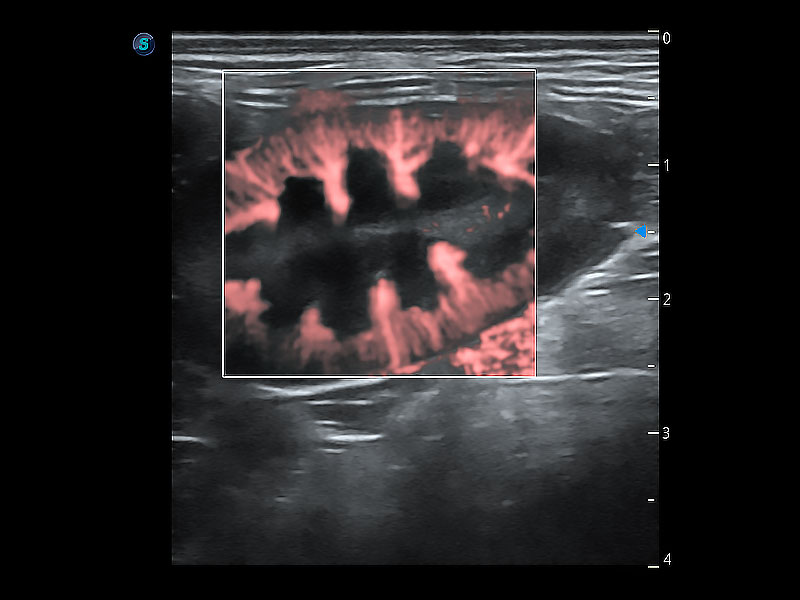

优异的基础图像

ProPet 80 全新的动物超声智能软件和丰富的探头群,为动物医生提供了高清晰度和精细分辨率的图像,无论在宠物、马科、畜牧还是实验室动物等应用中都可以轻松应对,为您的日常工作带来满意的体验。

(犬)肾脏显微血流